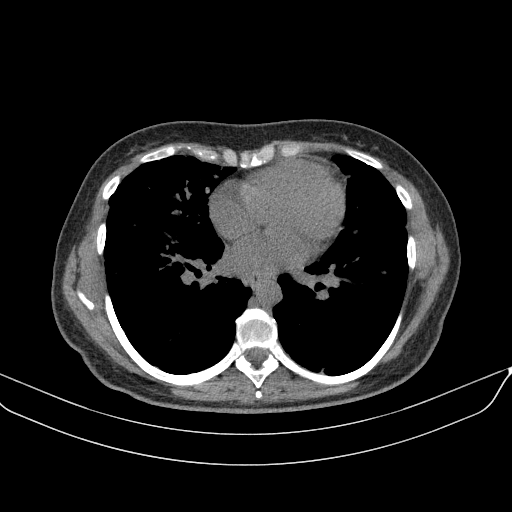

Original VENOUS CT scan

Full window (WL 1023.5, WW 4095 β†’ Low βˆ’1024, High +3071)

Lung window (WL -600, WW 1500 β†’ Low βˆ’1350, High +150)

Mediastinum window (WL 40, WW 400 β†’ Low βˆ’160, High +240)